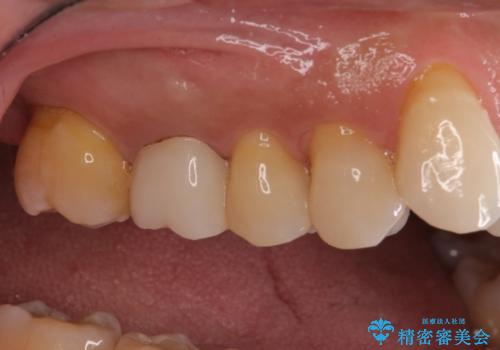

左上で効果を実感して頂き、その後右上もご希望されました。合計3本の歯を治療しました。

腫れもなくなり、見た目もきれいになったため、右上もご希望されて計3本の歯を治療しました。患者様には大変満足して頂きました。